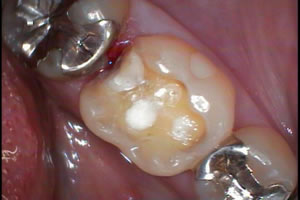

新しい銀歯をいれます!

なるべく大きくならないように削りますが、、、

削るたびに銀歯は大きくなります!歯質は削られるのです、、、

銀歯の金属は硬くて強い材料ですが、どうしても接着剤には限界が

あります!世の中に絶対に外れない接着剤はありません!

楯と矛みたいなお話し、、、

外れそうになっていないかの定期検診も大切ですね~!!! |